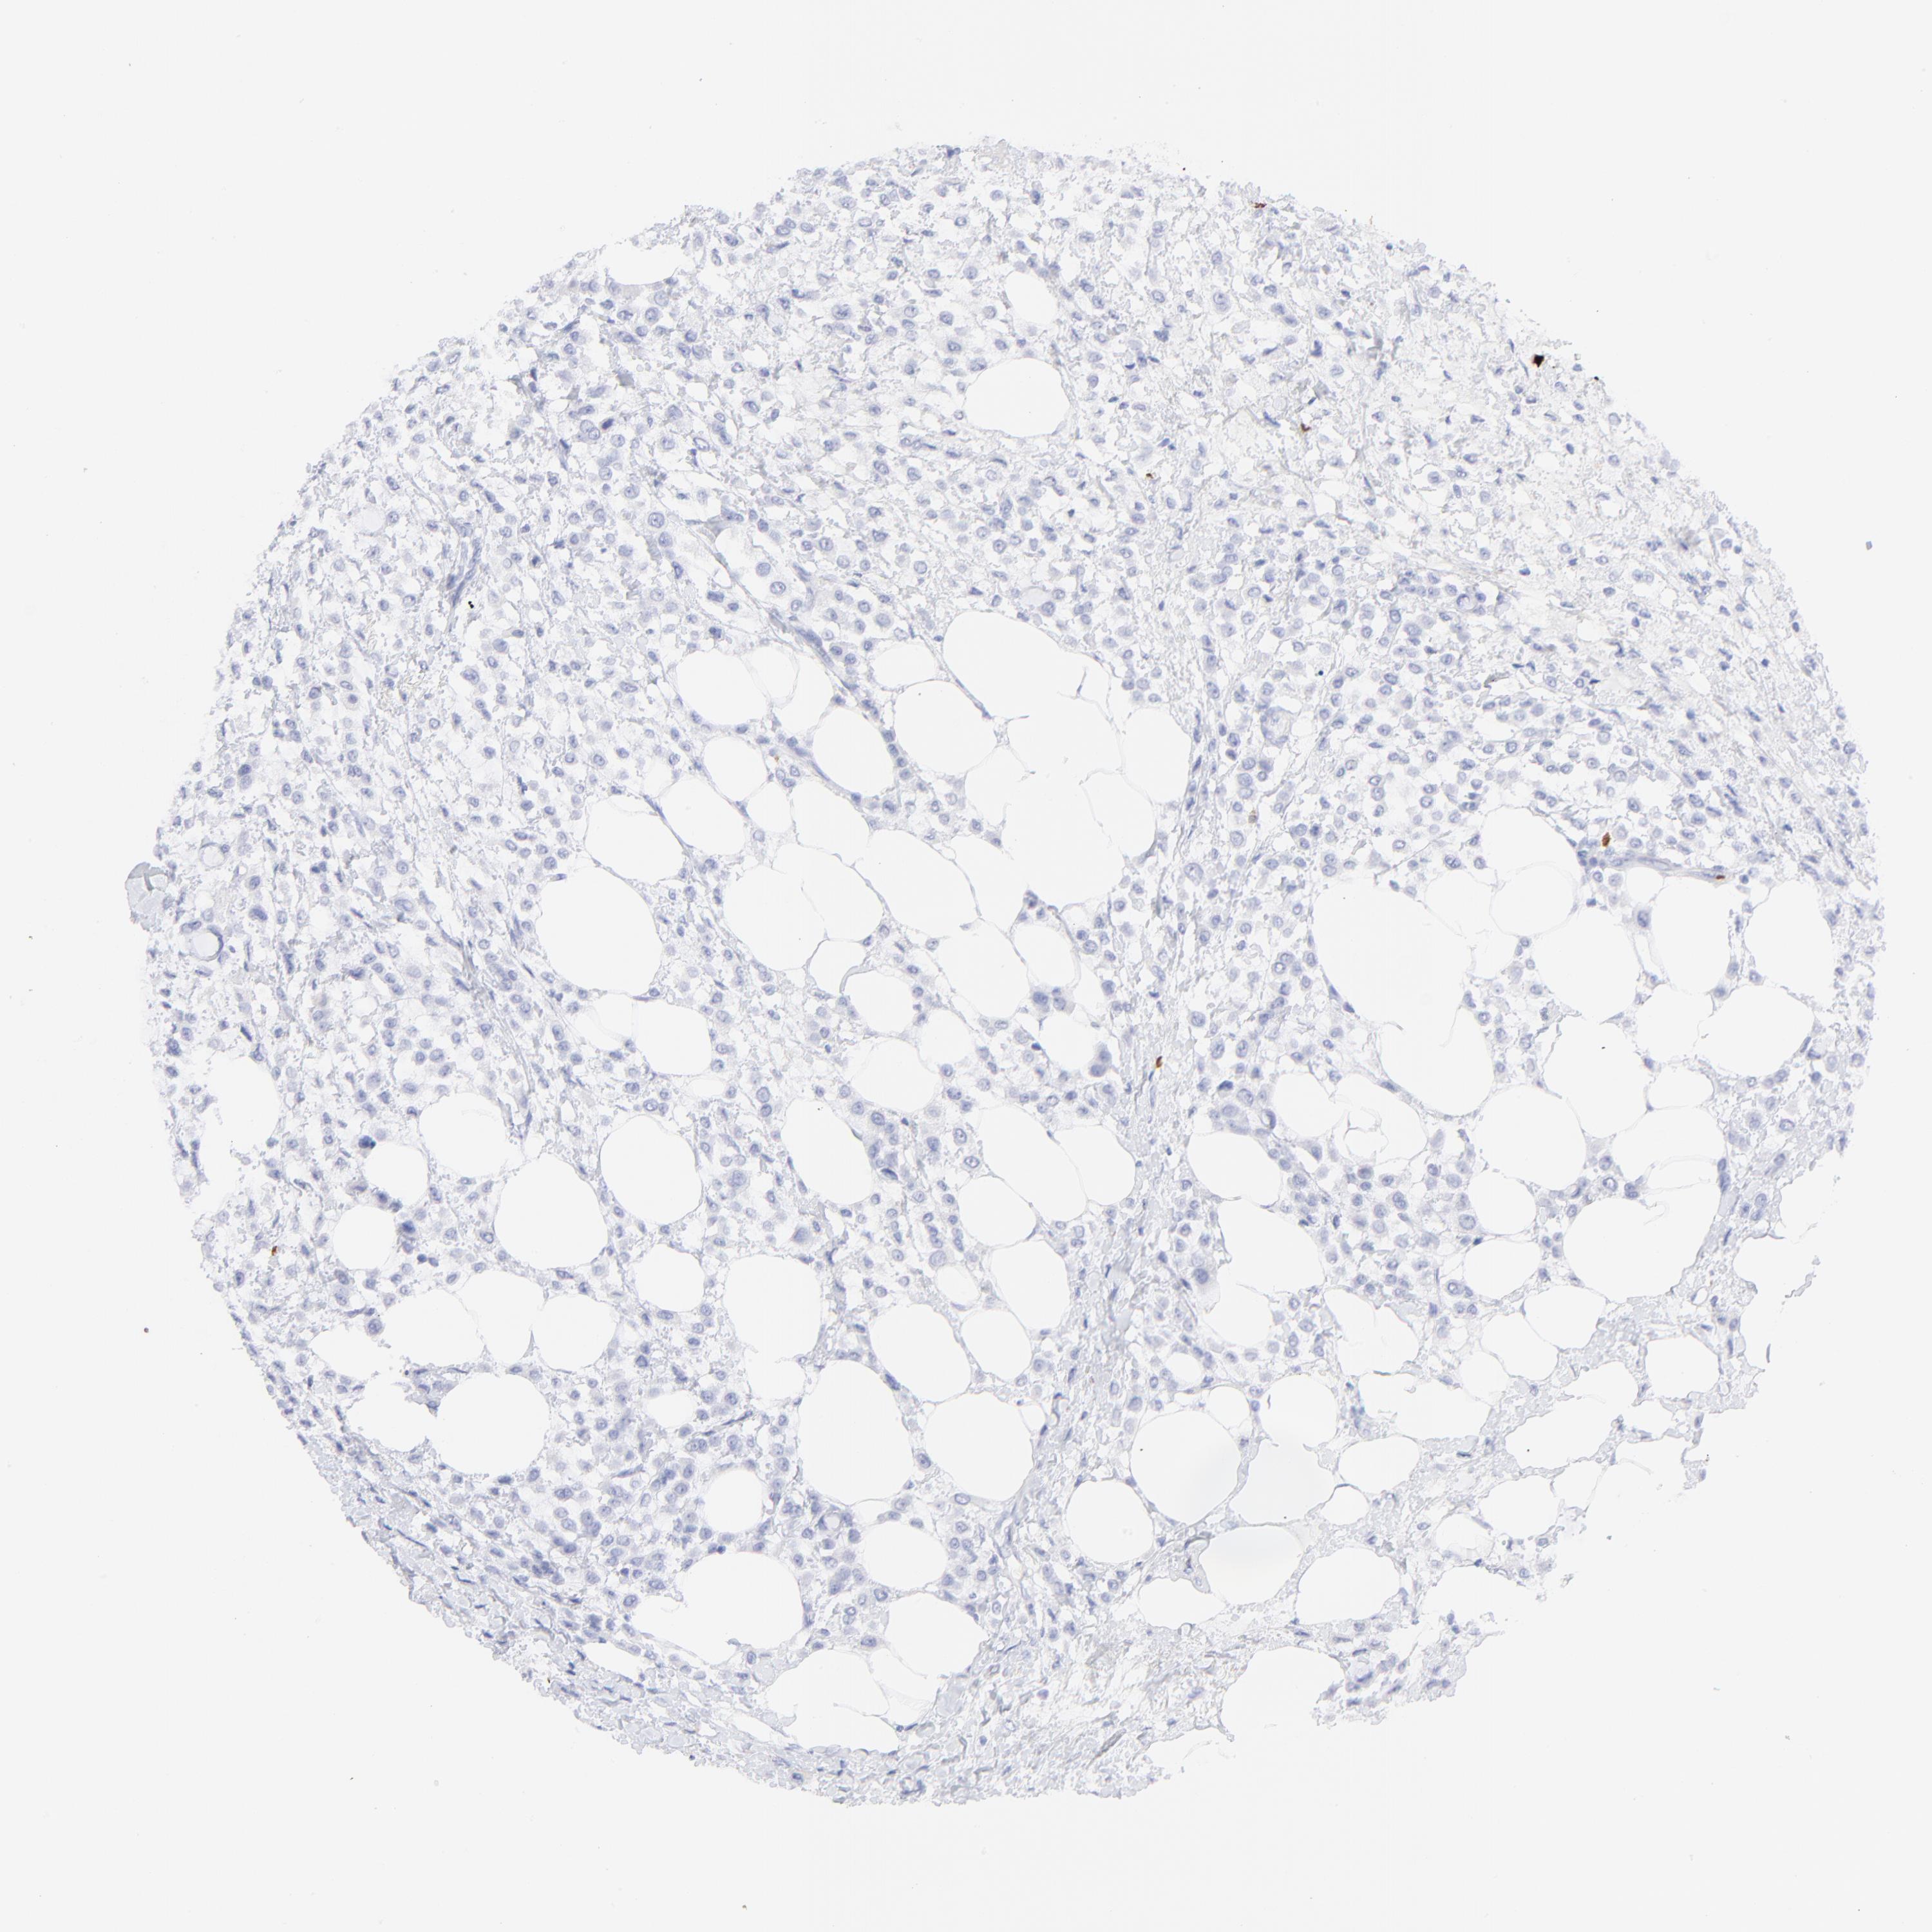

CANCER BREAST CANCER Show tissue menu

BRCA TCGA BRCA VALIDATION PROTEIN EXPRESSION